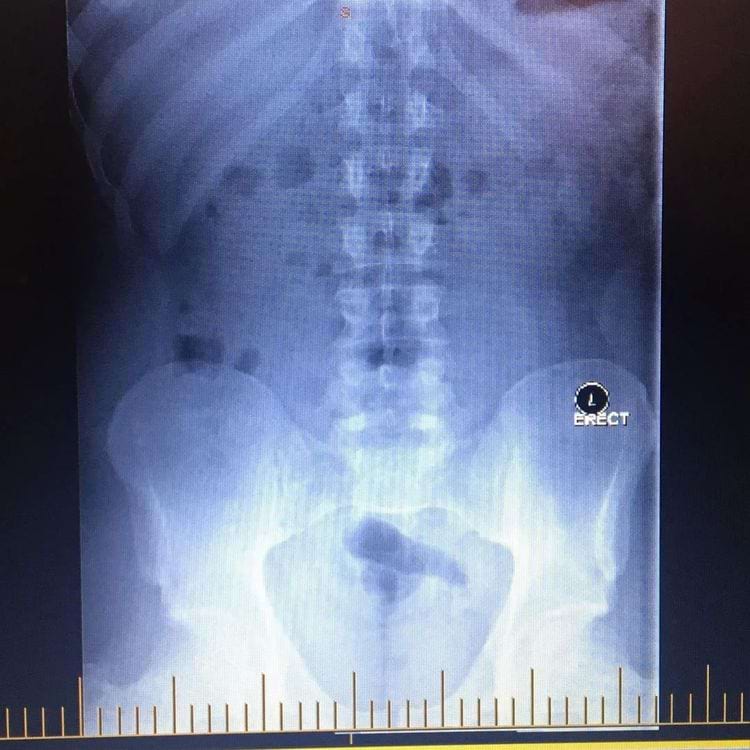

Вот как выглядит на рентгеновском снимке, когда вы сдерживаете газы (воздушный карман между костями таза)